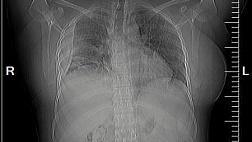

Пациентка переведена к нам в отделение торакальной хирургии из родильного отделения. Будучи беременной на 9 месяце COVID-19 с возникновением двухсторонней вирусно-бактериальной пневмонии с деструкцией в нижней доле правого легкого, эмпиемой плевры и бронхоплевральным свищем. По данным Р-КТ органов грудной клетки: полость деструкции в нижней доле правого легкого. Выполнено дренирование плевральной полости справа. У пациентки – утечка воздуха по дренажу из плевральной полости. 05.06.2020 выполнена клапанная бронхоблокация промежуточного бронха (блокатор Medlung №12) с хорошим клиническим эффектом (сброс воздуха по прекратился через 6 часов после вмешательства). Но, через 2 дня пациентка откашляла блоктор.